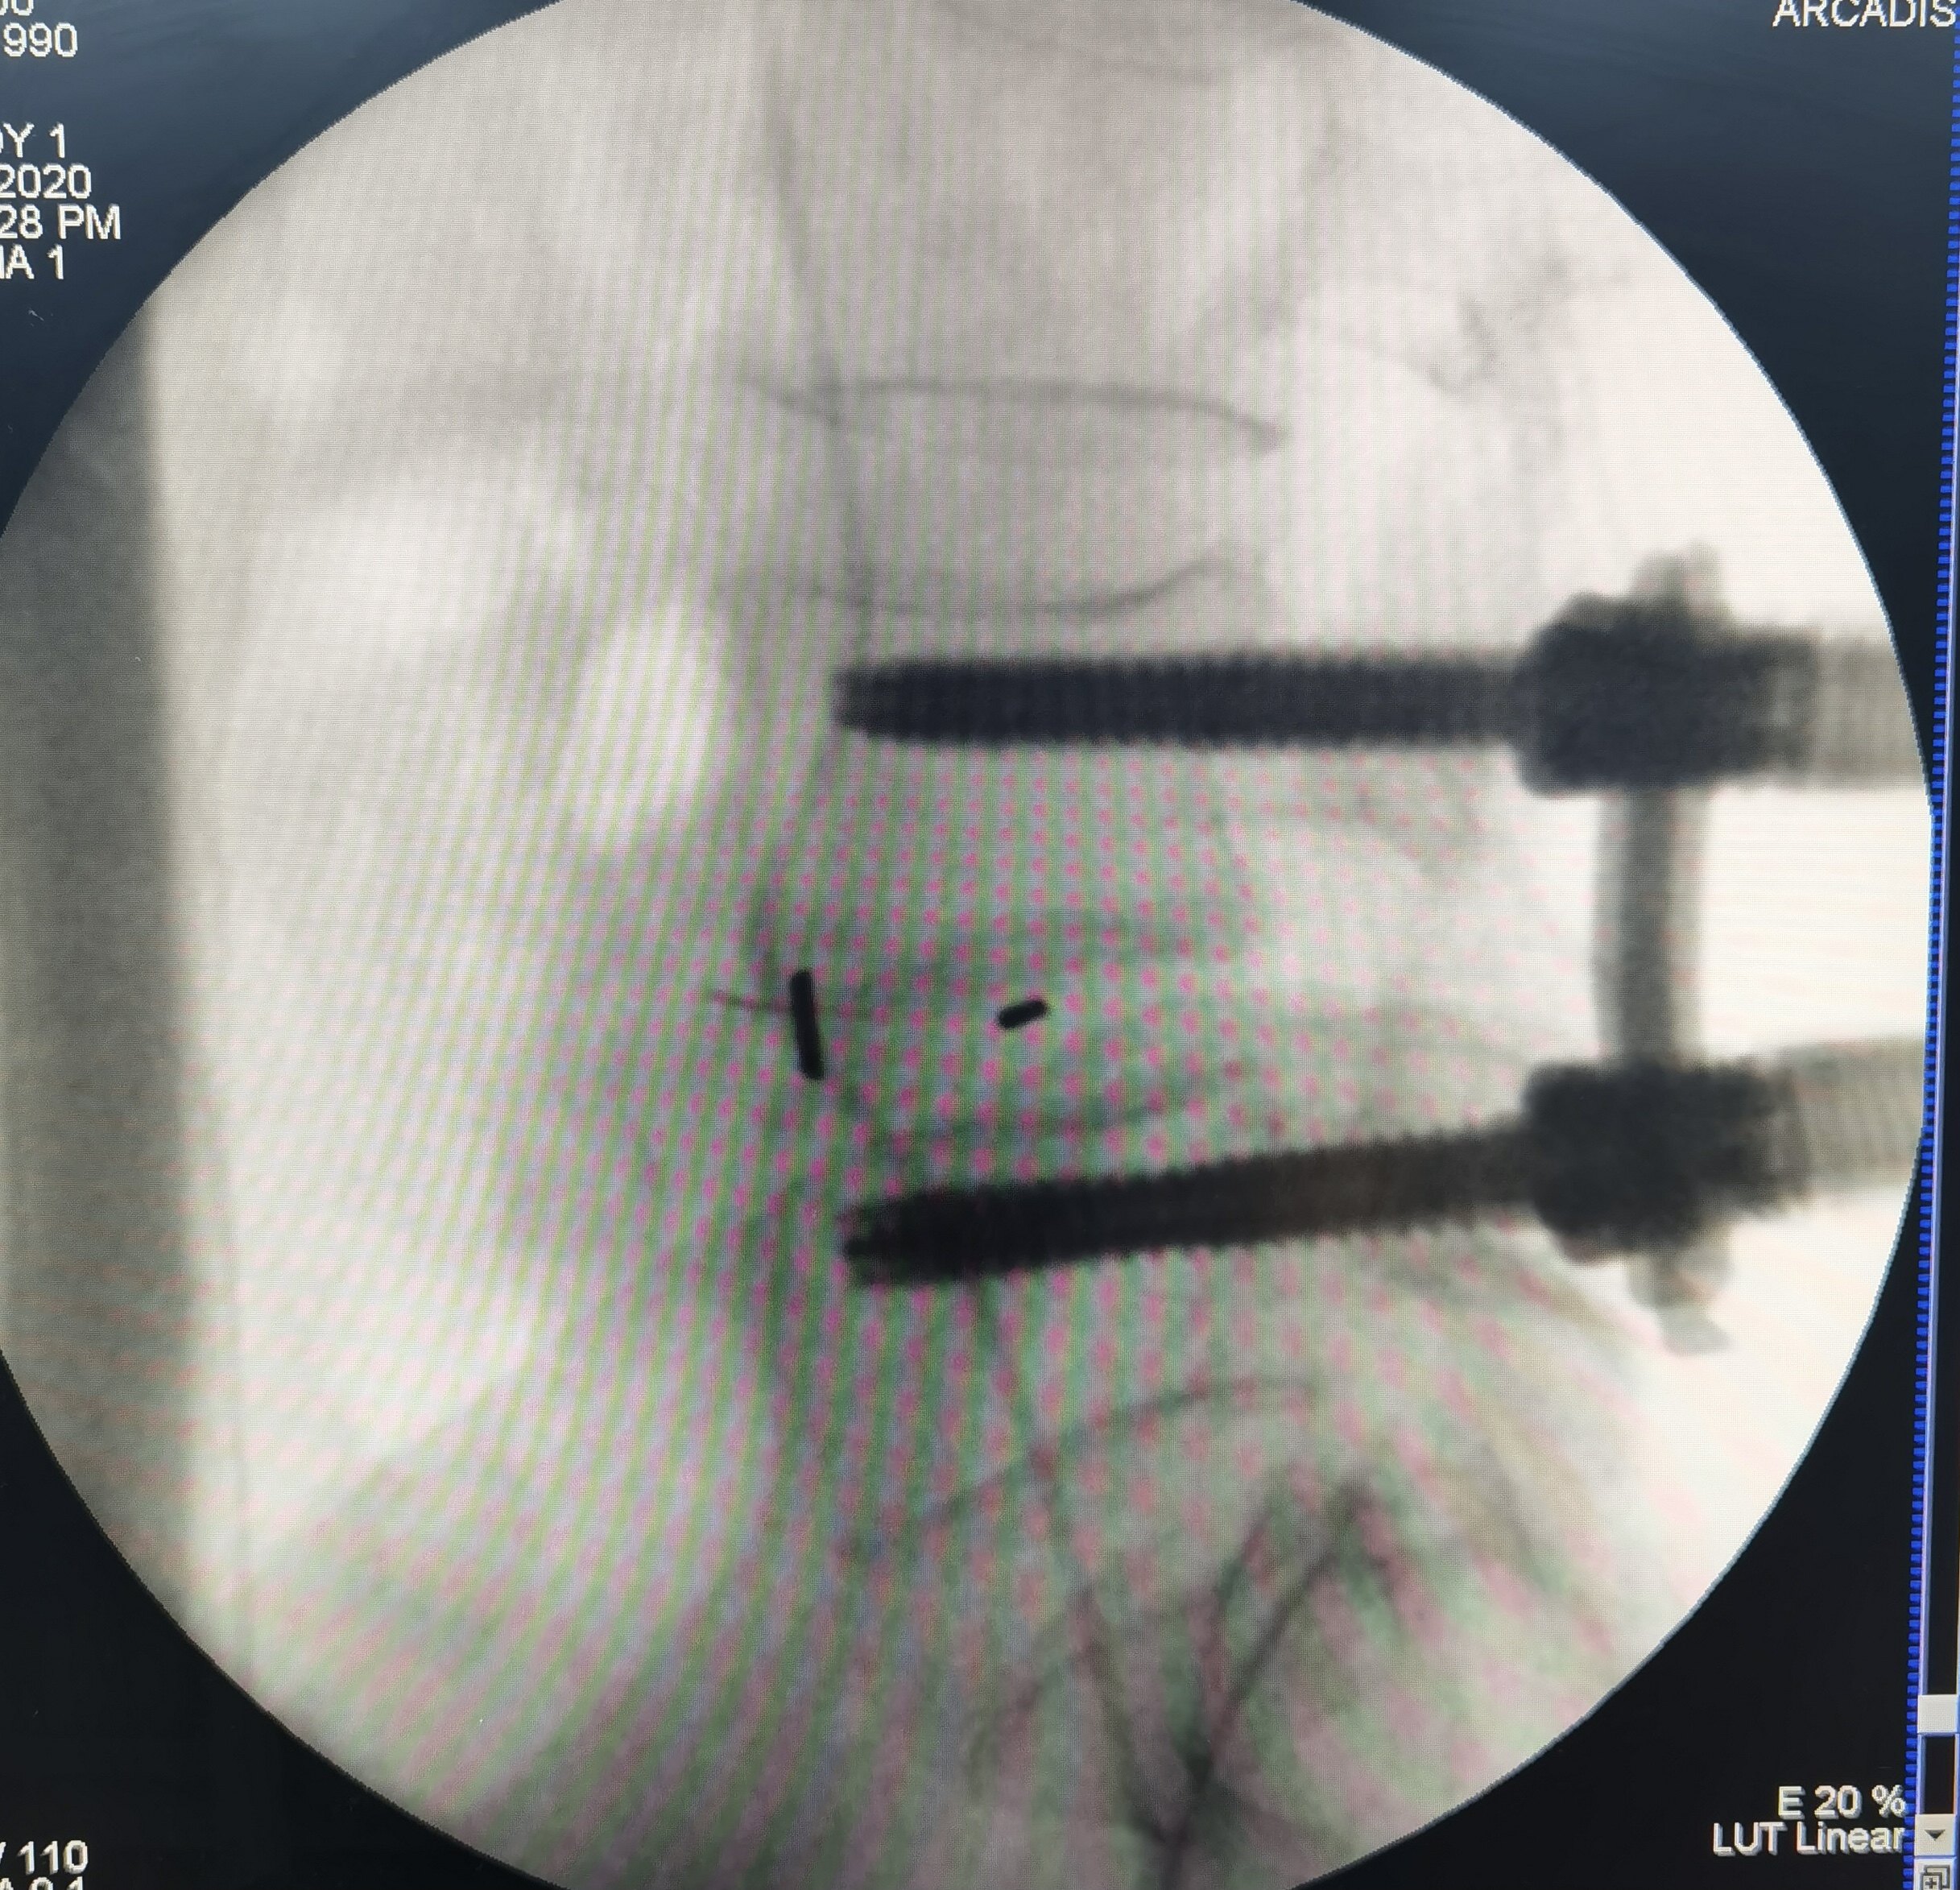

微创内窥镜治疗腰椎滑脱X光片的侧位透视片